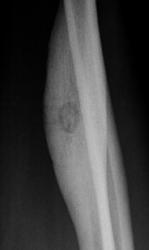

Татьяна Валентиновна представила интересный, классический случай "Остеоид-остеома".

Татьяна Валентиновна обращает внимание, что в данном случае имеют место, все классические признаки данного патологического процесса:

- выраженный гиперостоз;

- очаг разряжения - "гнездо";

- с более плотным включением - "яйцо в гнезде".